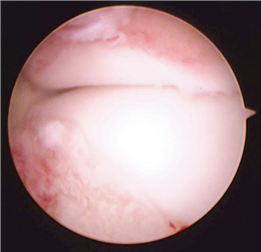

First MTP Arthrodesis

In cases of end-stage hallux rigidus, first MTP arthrodesis yields excellent, predictable outcomes. A dorsal longitudinal incision is made just medial to the EHL tendon. The joint is exposed, and aggressive cheilectomy is performed to remove all dorsal, medial, and lateral osteophytes. The remaining articular cartilage on the metatarsal head and the base of the proximal phalanx is resected using cup-and-cone reamers, which allow for infinite adjustment of the joint position prior to fixation.

Positioning of the fusion is the most critical step of the operation. The hallux must be positioned in 10-15 degrees of valgus, 15-20 degrees of dorsiflexion relative to the first metatarsal, and neutral rotation. Excessive dorsiflexion causes shoe impingement, while insufficient dorsiflexion leads to vaulting during gait and interphalangeal joint arthritis. Fixation is most reliably achieved using a pre-contoured dorsal locking plate combined with a lag screw crossing the fusion interface.